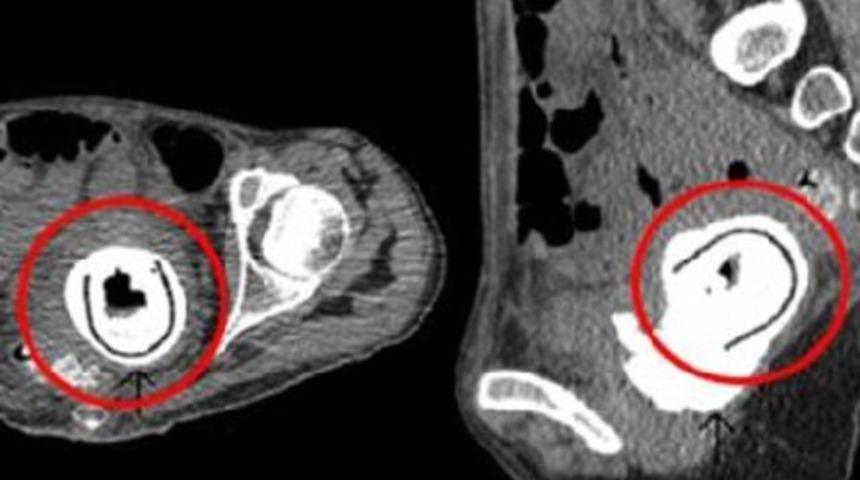

İskoçya’da 38 yaşındaki bir kadın idrara çıkarken ağrılar hissetmesi sonucu doktora başvurunca çekilen röntgeninde vajinasında unutulmuş bir vibratör bulundu. Herkesi şaşkınlığa uğratan vibratörün uzunluğunun 12 cm olduğu açıklandı.

İspanyol basınında yer alan haberde, doktorlar ilk defa böyle bir olayla karşılaştıklarını vurgulayarak 12 cm uzunluğundaki bir vibratörün 10 yıl boyunca son derece hassas bir bölge olan vajinada kalmasının imkansızlığına değindiler. İskoçyalı kadın ise yaptığı açıklamada en son 10 yıl önce çok sarhoş olduğu bir gece sevgilisi ile beraber olurken vibratör kullandığını söyleyerek “O gece neler oldu tam olarak hatırlayamıyorum, sanırım o zaman unuttum” dedi. Başarılı bir ameliyat sonrası vajinadan çıkartılan vibratörün özel olarak korunduğu ve çok yakında açık artırma sonrası satışa çıkartılabileceği belirtiliyor.